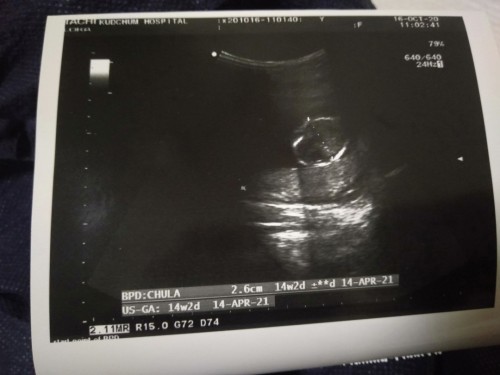

ตรงนี้คือศีรษะของน้องใช่มั้ยคะ พอดีไปตรวจคัดกรองดาวซินโดรมค่ะ ลืมถามหมอ #ขอบคุณล่วงหน้านะคะ

ใช่ค่ะ หมอจะดูขนาดกระโหลกศีรษะก่อนเป็นอันดับแรก